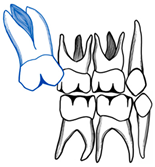

| Barberia-Leache ’s Classification (Based on the effect on second primary molar) * | |||||

| Grade 1 Mild | Grade 2 Moderate | Grade 3 Severe | Grade 4 Very severe | ||

| Limited resorption to the cementum or with minimum dentine penetration | Resorption of the dentine without pulp exposure | Resorption of the distal root leading to pulp exposure | Resorption that affects the mesial root of the second primary molar | ||

![]() | ![]() | ![]() | ![]() | ||

| Harrison and Michal’s Classification (based on severity of the lock using bitewing radiograph) * | |||||

| Normal | Minimal lock | Severe lock | |||

| No sign of impaction | Impacted less than half the width of the distal marginal ridge of the second primary molar | Impacted more than the width of the distal marginal ridge of the second primary molar | |||

![]() | ![]() | ![]() | |||